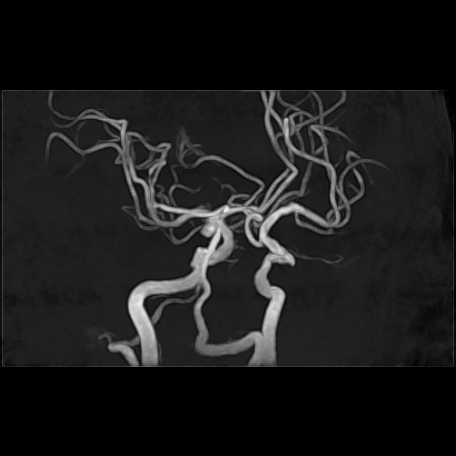

MRI検査

頭部

脳動脈瘤